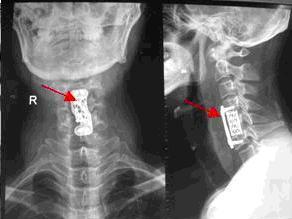

1.X線平片及動力性側位片

2.MRI技術

MRI圖像如一幅脊髓及其周圍組織的縱向剖面解剖圖,可使局部的病變一目了然,所以每個病例均應爭取選用,這不僅對頸椎病的診斷,分型至關重要,且為手術的決定,手術部位的判定及術式的選擇等都具有重要意義。

3.其他

包括CT檢查,脊髓造影等對本型的診斷均有作用,可酌情選擇。